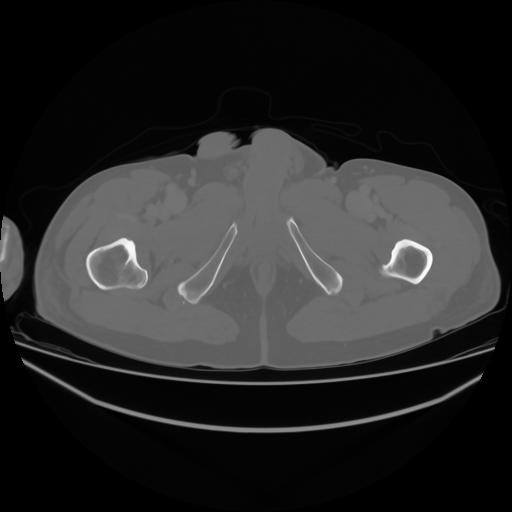

4 CUERPO,CE,Axial,3.0,CUERPO,,